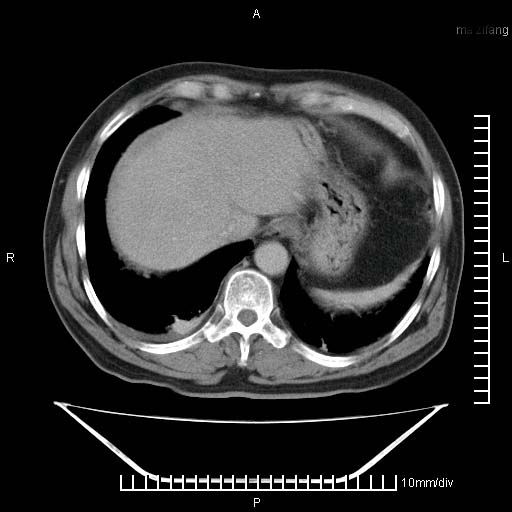

标题: CT25082:肝脏增强:男性,70岁 [打印本页]

标题: CT25082:肝脏增强:男性,70岁

患者以心脏疾病收住院,腹部无明显症状,b超查肝脏有占位。

增强效果不理想。考虑转移,胆囊壁明显增厚,不排除胆囊癌肝转移。

病灶无强化,考虑囊肿。

牛眼征,中心坏死无强化,外缘强化,最外缘又见低密度,考虑转移,与脓肿鉴别

肝内多发转移瘤,右下肺炎症并少量胸水。胃壁增厚建议胃镜,胰尾部“病变”为肠管。

1)肝脏多发性转移瘤(不排除胰尾癌转移所致可能)。2)腹水。3)右侧少量胸腔积液。

ct25082 结果:转移瘤

外院mr结果:胰尾恶性占位。